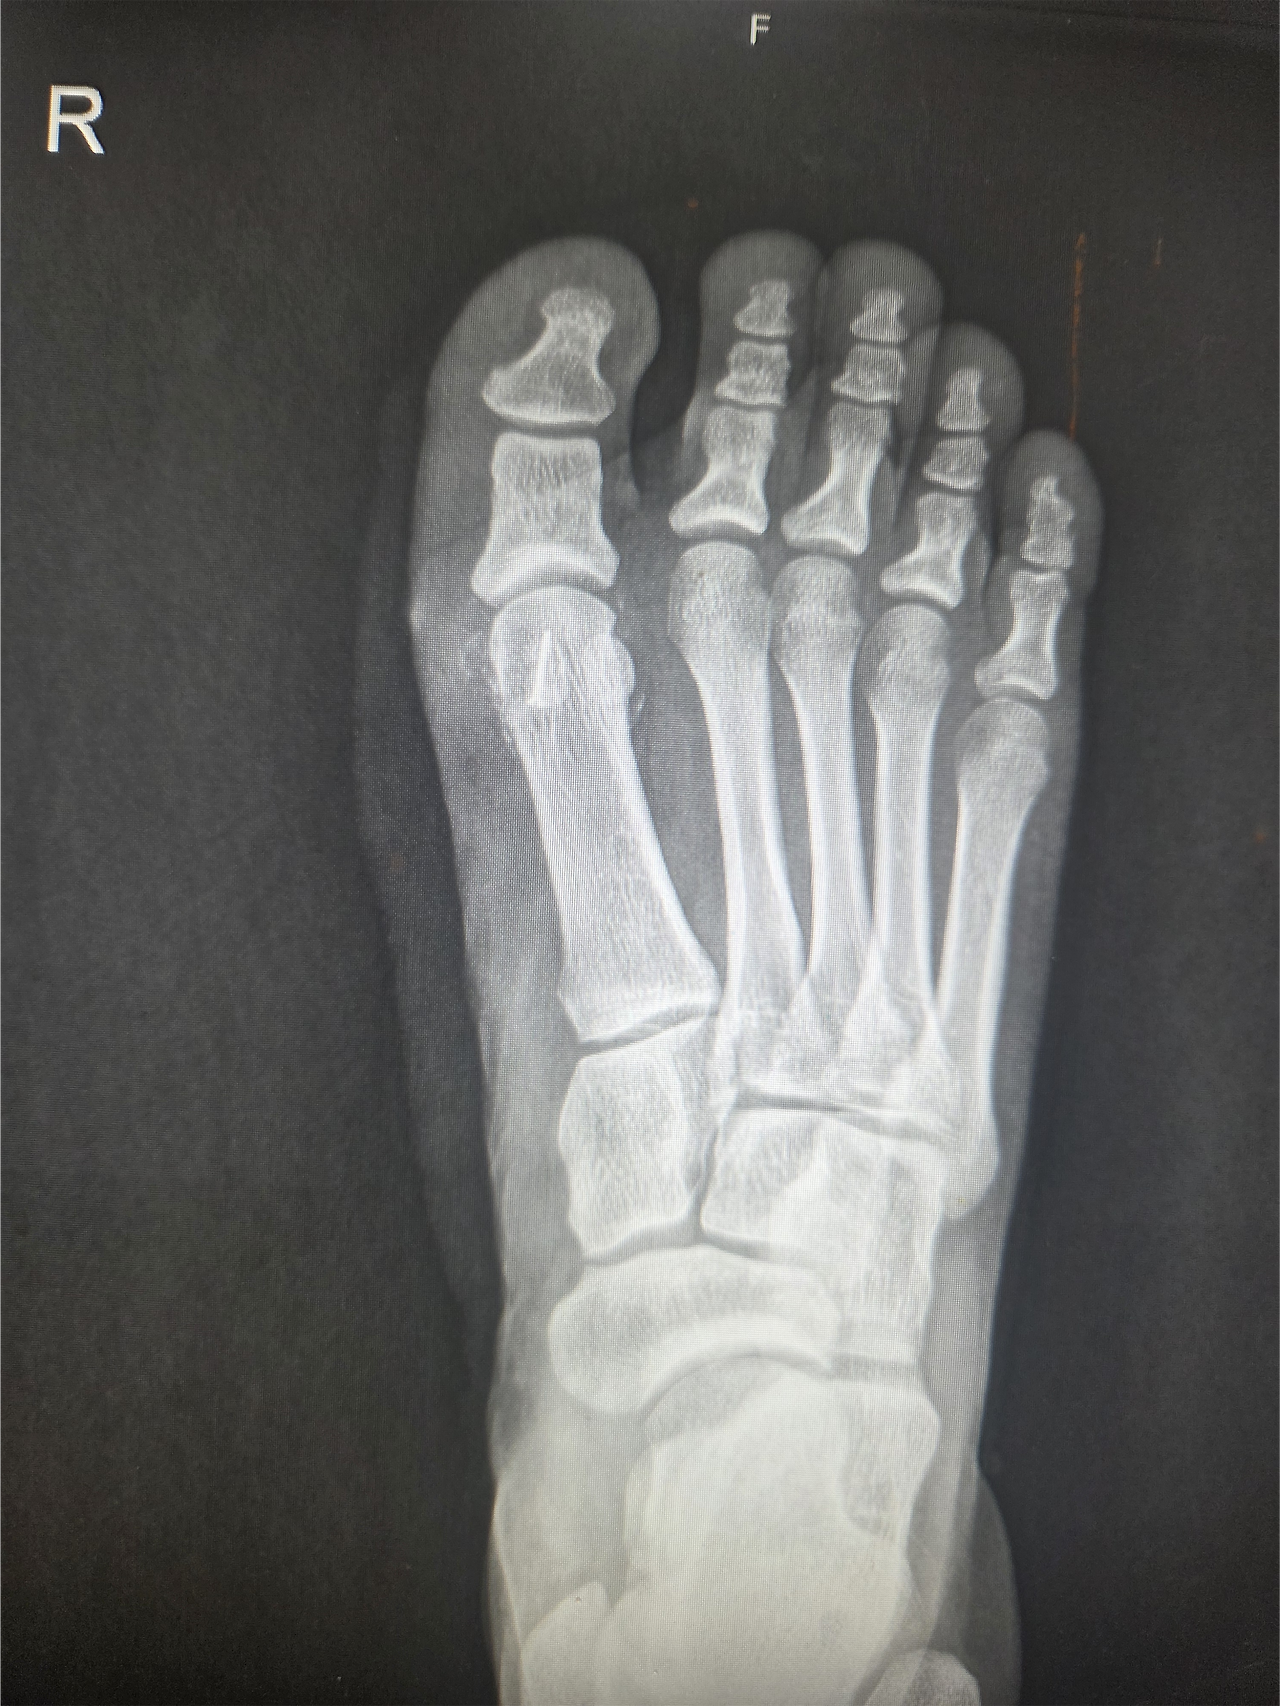

그가 처음 내 진료실을 찾은 것은 2024년 11월이었다. 당시 그는 이미 6개월 이상 엄지발가락 통증에 시달리며 여러 병원을 전전하던 상태였다. 깁스와 목발, 물리치료와 주사 치료까지 해볼 수 있는 건 다 해봤지만, 통증은 날카롭게 찢어지는 듯 심해졌고 보행조차 점차 어려워지고 있었다. 우선 시행한 X-ray 검사에서 통증 부위인 우측 종자골이 두 조각으로 나뉜 '이분 종자골' 형태가 확인되었다.

특이한 점이 있었다. 보통 이분 종자골은 80% 이상의 환자에서 양쪽 발 모두 관찰되는데, 이 환자는 유독 통증이 있는 우측에만 존재했다. 물론 한쪽만 이분 종자골인 경우도 드물지 않고, 환자의 직업 특성상 발에 충격이 잦아 '종자골염'일 가능성도 컸다.

하지만 증상이 계속 악화되고 있다는 점, 그리고 이분 종자골을 가진 사람도 사이 연골 결합이 손상되면 골절과 같은 양상의 통증을 느낄 수 있다는 점에 주목했다. 나는 환자에게 '종자골 골절'의 가능성을 설명하고 CT와 MRI 등 정밀 검사를 진행했다.